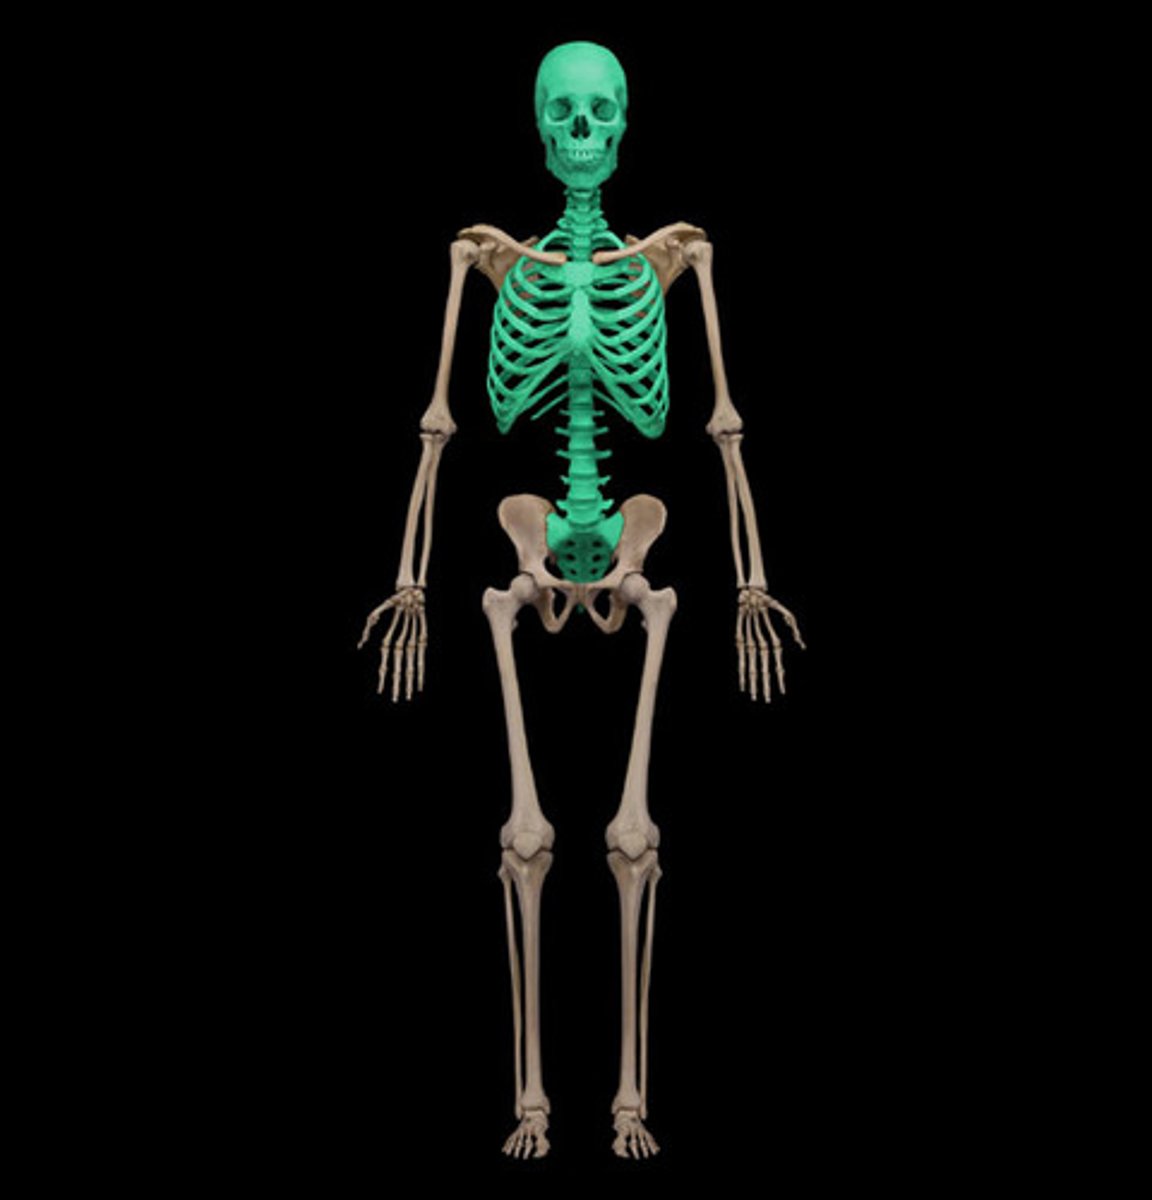

What bones are in the axial skeleton?

skull, vertebral column, ribs, sternum

How many bones are in the axial skeleton?

80